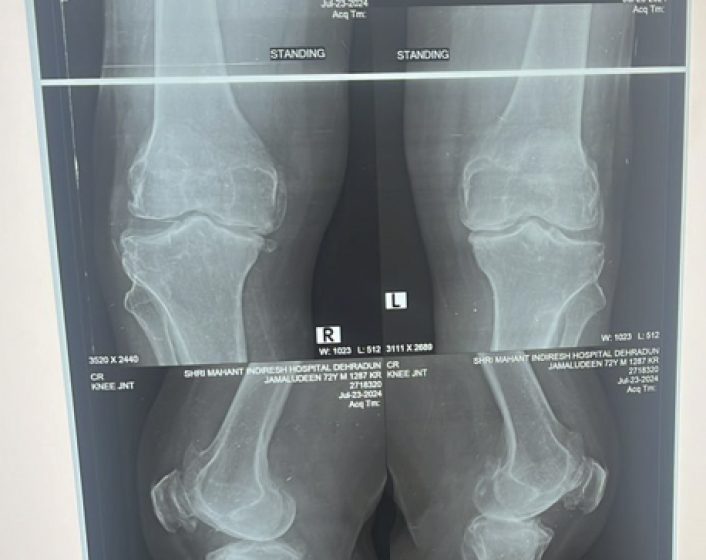

Genuine varum deformity in knee arthritis

End stage arthritis of knee